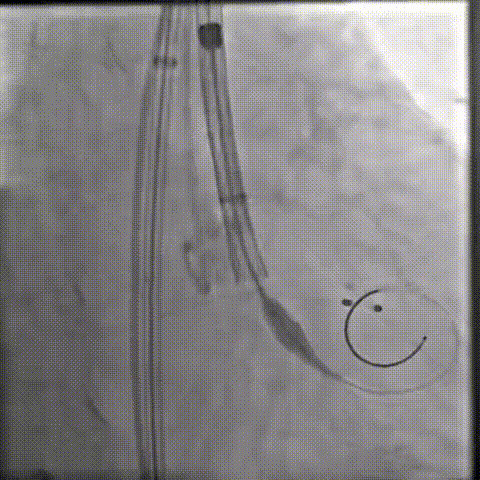

20球囊预扩

器械过弓柔顺

初始定位